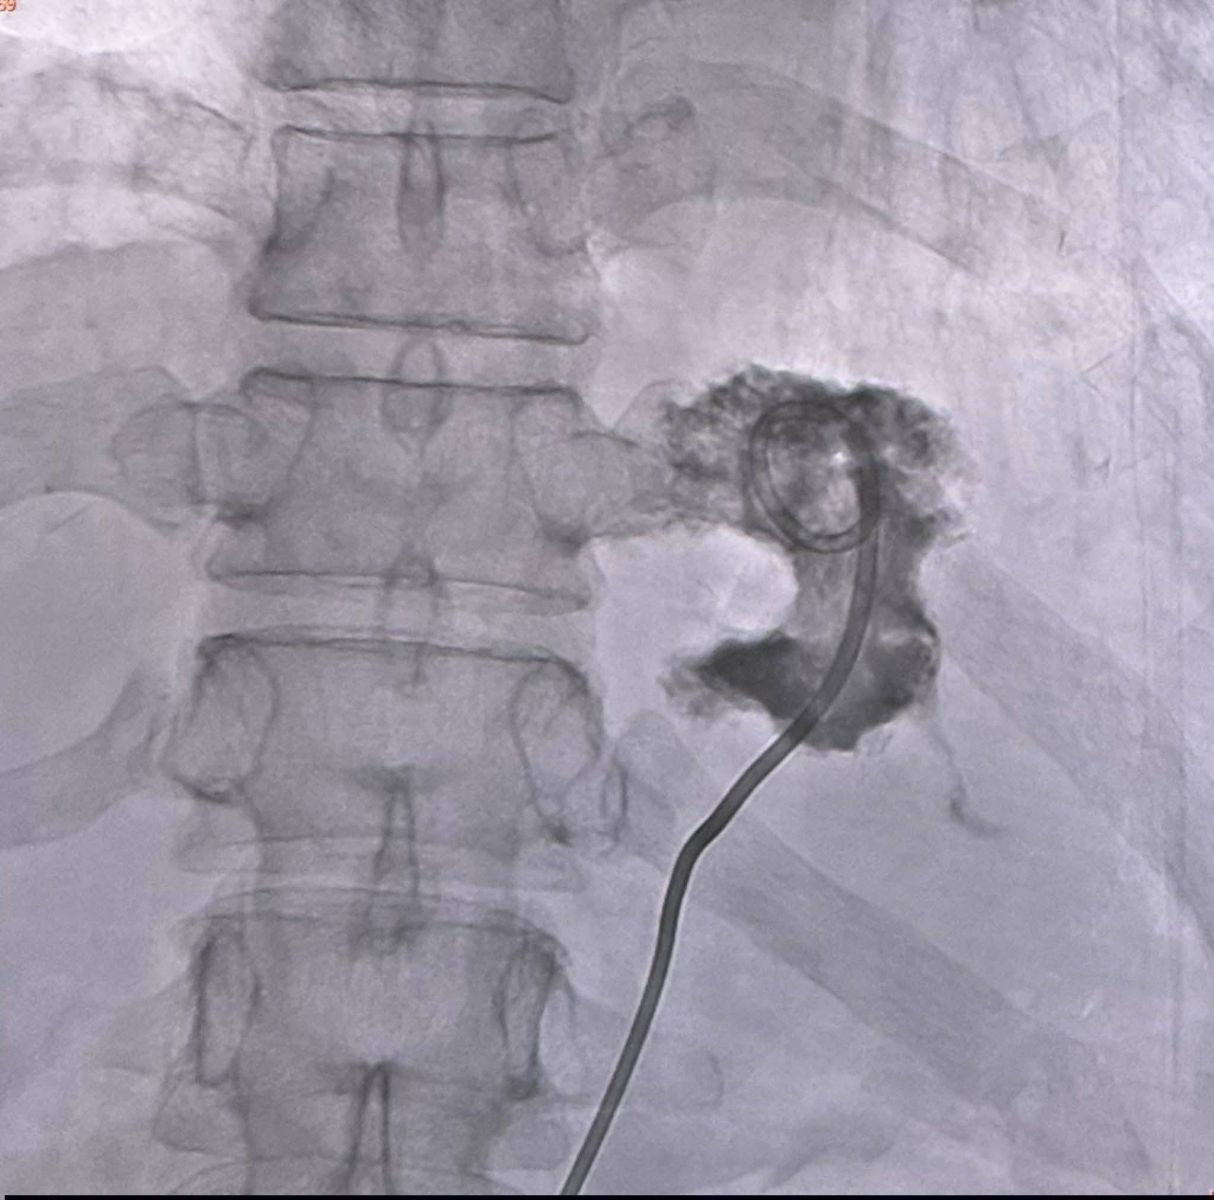

ทำการเจาะฝีในตับ ได้หนองข้นสีเหลือง 70 ซีซี (ดูรูป) ใส่สายระบายหนอง (ดูรูป) คาไว้ 5 วัน ถอดสายเมื่อไม่มีหนองไหลออกมาอีก เพาะเชื้อจากหนองในตับขึ้นเชื้อแบคทีเรีย Klebsiella pneumoniae ไวต่อยา Ceftriaxone และยา Levofloxacin ให้ยาปฏิชีวนะ Ceftriaxone ทางเส้นเลือดตั้งแต่วันแรกที่เข้านอนในรพ. ไข้ลง กินอาหารได้มากขึ้น อยู่โรงพยาบาล 7 วัน ให้กลับบ้านได้นัดมาฉีดยา Ceftriaxone วันละครั้งอีก 2 สัปดาห์ หลังจากนั้นเปลี่ยนเป็นยากิน คงต้องให้การรักษาฝีในตับด้วยยาปฏิชีวนะอย่างน้อย 2 เดือน